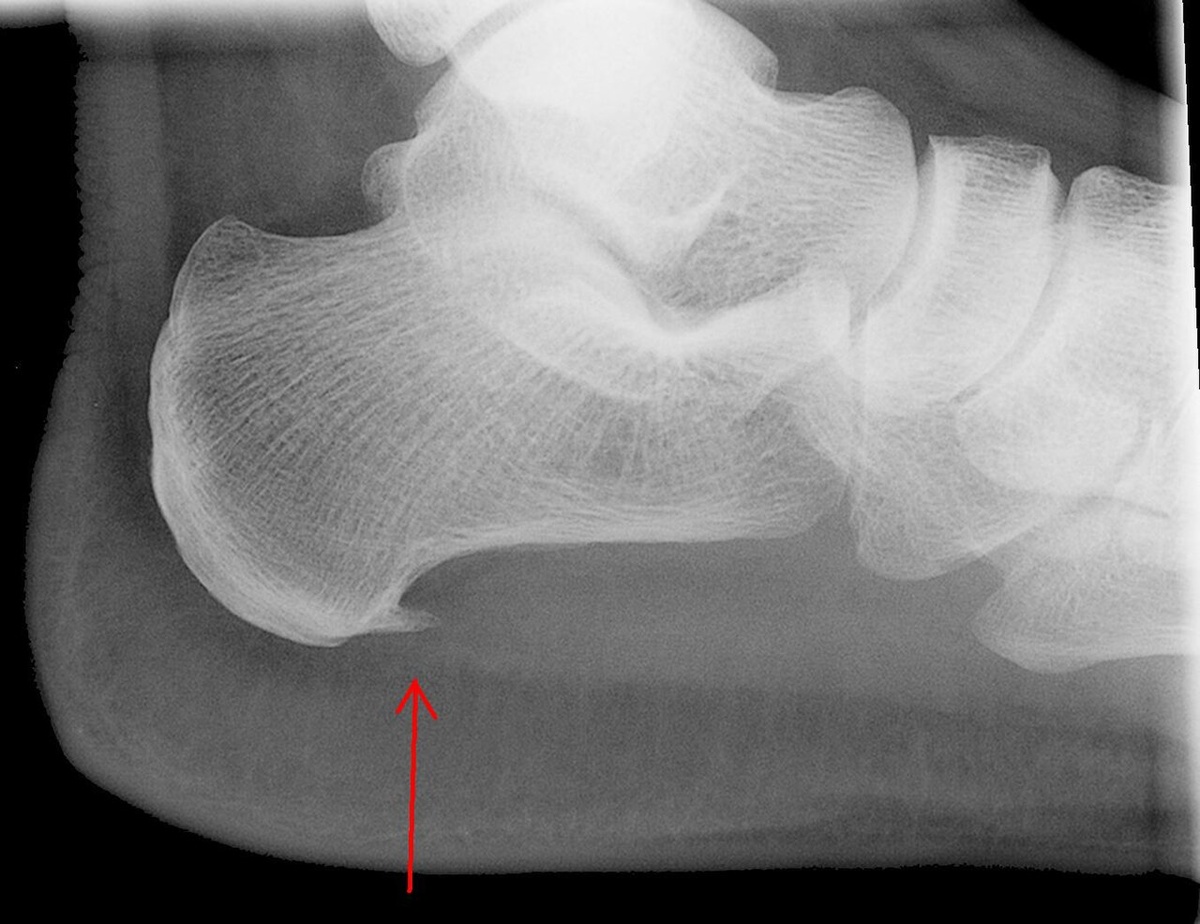

На снимке — классическая шпора.

Рис1. На рентгенограмме показана пяточная шпора

А костный «шип» на рентгене — это просто след хронической перегрузки.